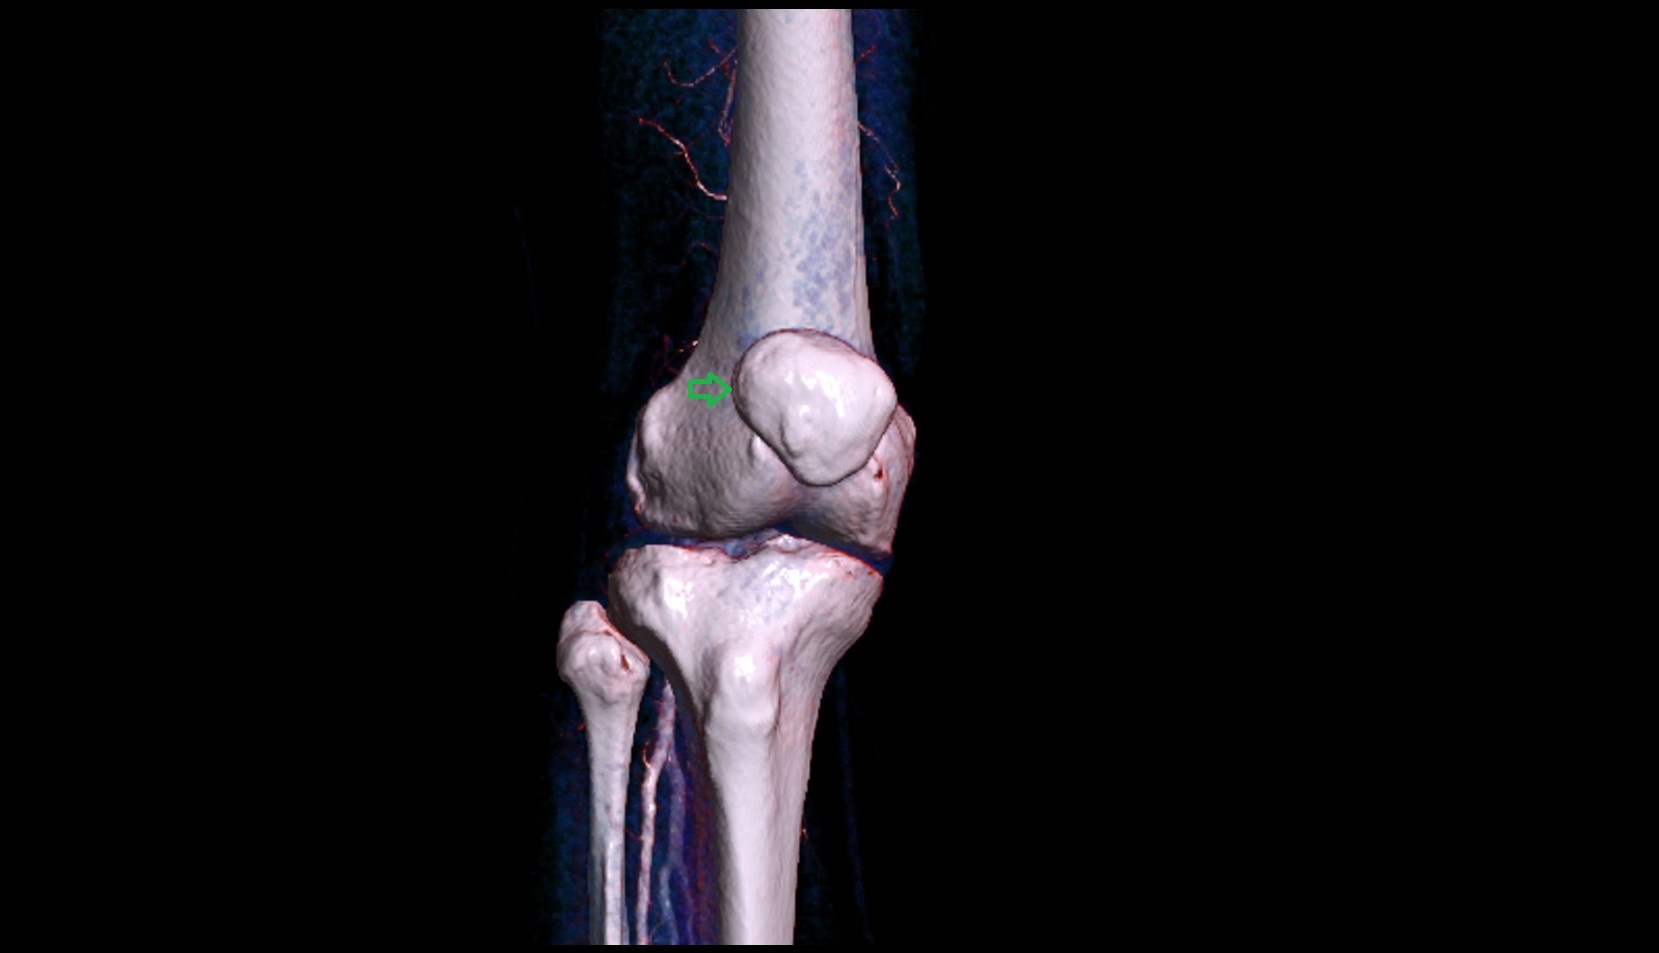

- Medial epicondyle of femur

- Lateral epicondyle of femur

- Lateral condyle of femur

- Medial condyle of femur

- Knee Joint